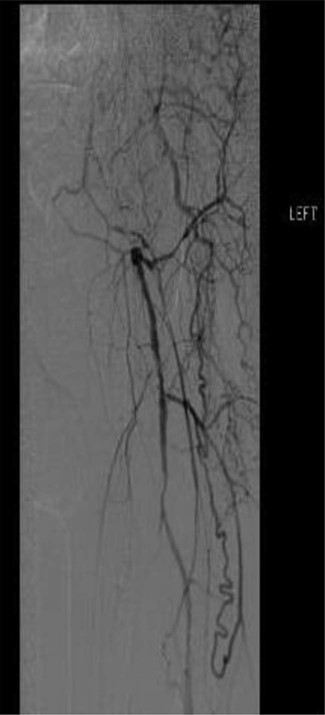

Workup began with noninvasive studies of the left lower extremity displaying aortoiliac occlusive disease and infrainguinal disease. Aortogram demonstrated a severely calcified aorta, patent left common iliac and proximal hypogastric arteries, with occlusion of the left external iliac, left common femoral and left superficial femoral arteries (Fig. 1). The right iliac system was patent apart from an occluded right hypogastric artery. A selective left lower extremity angiogram demonstrated reconstitution of the mid-to-distal profunda femoris artery (Fig. 2) to the proximal above-knee popliteal artery at the adductor hiatus (Fig. 3). Extensive collateralization was appreciated in the pelvis and lower extremity, between the residual left hypogastric artery and profunda femoris artery. Endovascular revascularization attempts were unsuccessful.

Aortogram demonstrating occlusion of left distal hypogastric, external iliac and common femoral arteries, as well as right hypogastric artery